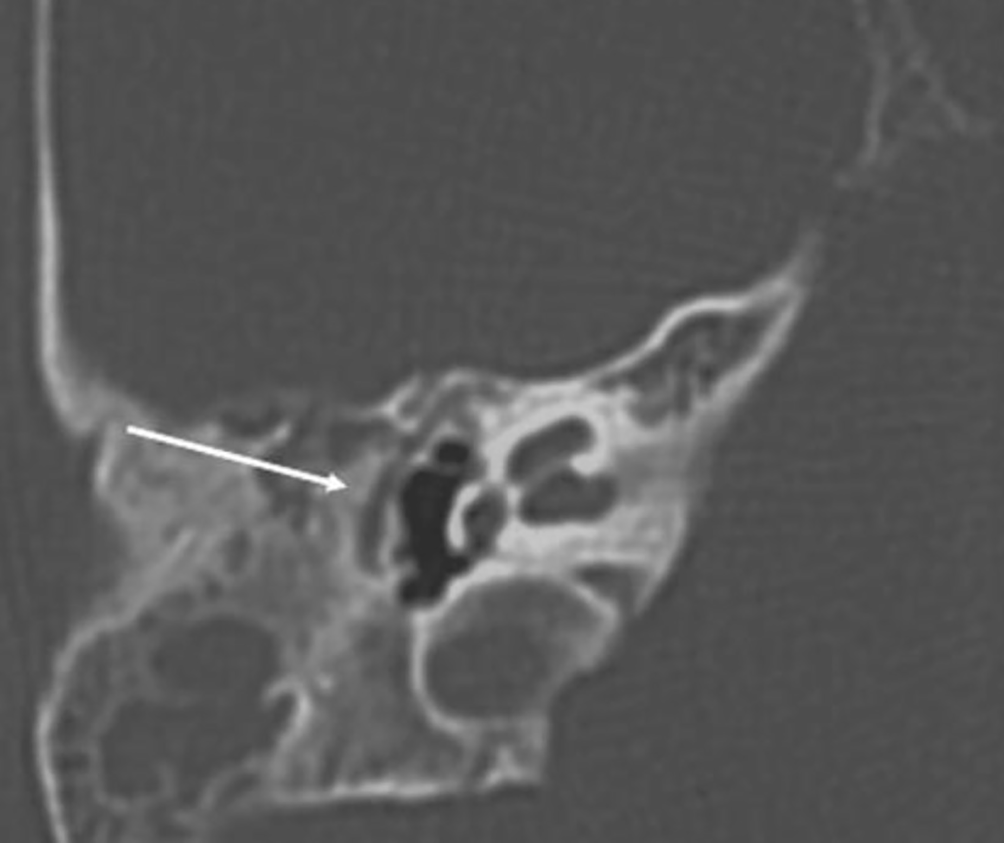

Die nachgewiesenen Dysplasien treten dabei unterschiedlich häufig auf. In etwa der Hälfte der Fälle findet sich bei Patienten mit höhergradigen Ohrmuscheldysplasien oder Gehörgangsatresien ein verminderte Mastoidpneumatisation, in fast 90 % der Fälle ist hier auch das Volumen der Pauke reduziert [25]. Ossikeldysplasien sind ebenfalls häufig. Oft zeigt sich ein dysplastisch verklumpter Hammer-Amboss-Komplex oder nur rudimentär angelegte Ossikelanteile. Der Stapes wird von allen Ossikeln (mit 31 % bei höhergradigen Fehlbildungen) noch am häufigsten angetroffen. Das runde Fenster scheint in 90 % der Fälle offen, während das ovale Fenster bei 40 % der Patienten mit Gehörgangsatresien und höhergradigen Ohrmuscheldysplasien verschlossen ist (Abb. 8). Der Verlauf des N. facialis ist bei mehr als 3 Vierteln der Patienten mit höhergradigen Dysplasien verändert. Im Mittelohr wird dabei oft eine Verlagerung nach kaudal, im Mastoid hingegen nach ventral beobachtet (Abb. 9). Der Austritt aus der Schädelbasis ist im Rahmen einer Gehörgangsatresie häufig weiter kranial. Entsprechende Kenntnisse sind zur Vermeidung intraoperativer Komplikationen von höchster Wichtigkeit. Assoziierte Fehlbildungen des Innenohrs wurden bis auf diskrete Veränderungen des lateralen Bogengangs in einer Analyse von Siegert et al. nicht beobachtet [25]. Diesbezüglich wird erneut auf die Bemerkungen im Abschnitt „Embryologie“ hingewiesen.

Abb. 8

Koronare Schichten der Felsenbein-Computertomographie eines 7‑jährigen Patienten mit linksseitiger Ohrmuscheldysplasie Grad II nach Weerda, nicht angelegtes ovales Fenster (roter Kreis). Ovales Fenster der Gegenseite normal angelegt (grüner Kreis). (Quelle: eigenes Bild des Autors)